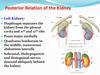

What are the posterior relations of the kidneys?

Posteriorly, kidneys are closely associated with the muscles of the posterior abdomenal wall:

- Superior pole is closely associated with the diaphragm

- Medially kidneys are closely associated with the PSOAS minor/major muscle

- ‘Middle laterally’ kidneys are closely associated with quadratus lumborum muscle

- Laterally the kidneys are closely associated with the trasversus abdominus muscle

Label this image